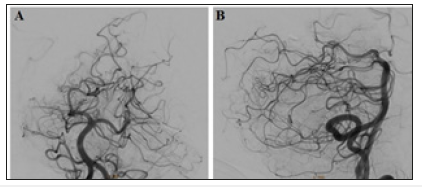

Figure 4:Follow-up after 3 months of right vertebral angiogram in case No.7 (A) Oblique (B) Lateral views showing incomplete closure of the AVM nidus and the patient was advised to consult gamma knife for the remaining nidus.

Follow-up control angiogram was done after 3 months that showed increasing nidal occlusion (about 90% closure). Also, the clinical status of the patient was improved, motor power improved (mRS 2) and total improvement of trigeminal nerve affection. showed the patient was advised to see gamma knife consultation (Figure 4)